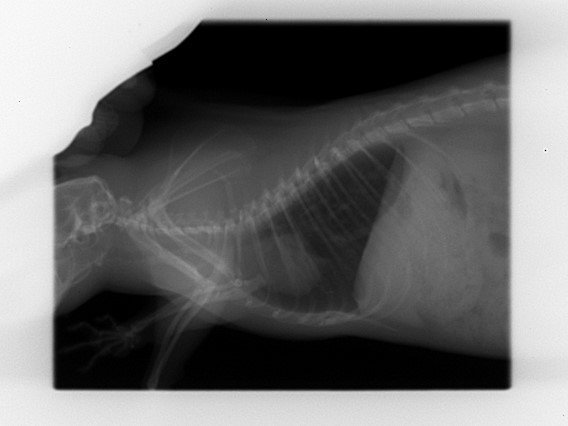

Découverte de multiples foyers infectieux dans les poumons :

Par radio, en janvier 2022.

A ce stade le véto n'est pas inquiet, car bien que multiples les tâches sont très infimes et les poumons restent intègres ; il me recommande de la surveiller de très près et me prévient que si une décompensation doit se faire se sera surement silencieusement (donc surveillance du poids et du mouvement respiratoire).

Le 25 mai je fais faire les radios de contrôle car je la trouve un chouya plus fine des flancs et on observe que l'aspect des foyers infectieux est plus "moucheté" ; c'est pas la cata encore (poumons toujours intègres) mais comme y'a tout de même évolution on commence le traitement : Doxy pour au moins deux semaines.

Voilà les radios ; pour chaque ligne :

• à gauche = janvier

• à droite = mai

KISS 2022 01 03 (1).jpgKISS 2022 05 25 (2).jpg

KISS 2022 01 03 (2).jpgKISS 2022 05 25 (1).jpg

• La radio montre que son cœur est légèrement décollé de l'endroit où il devrait être, mais sans que ça soit un soucis.